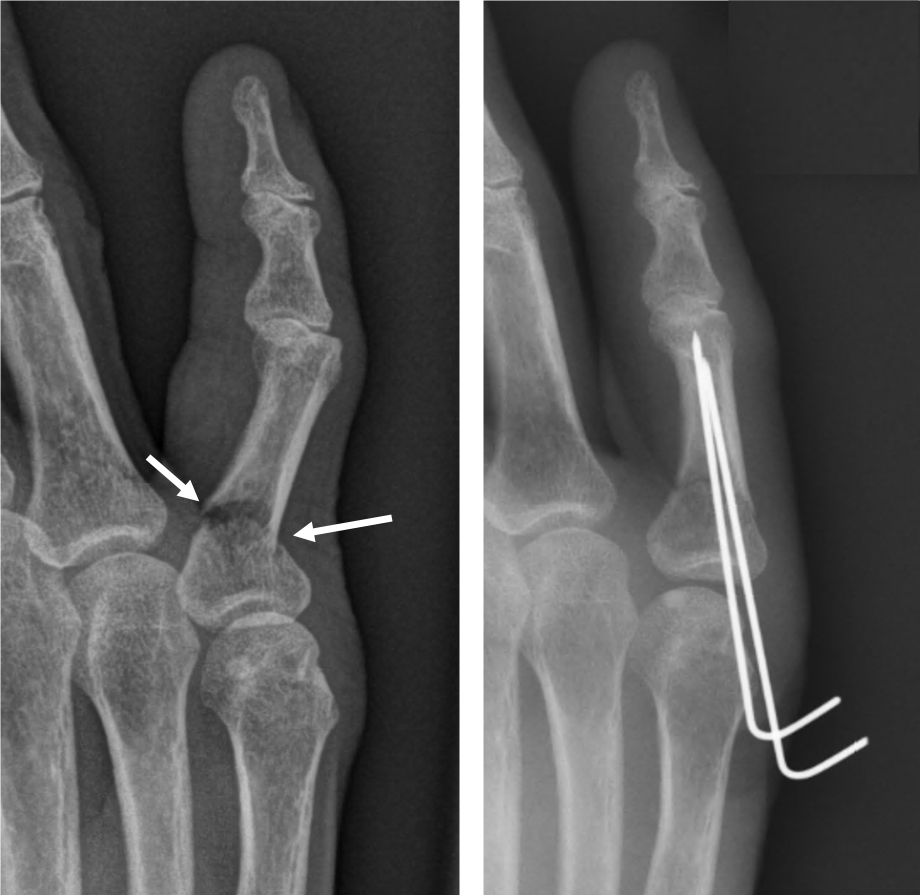

비전위성 골절(뼈가 어긋나지 않은 경우)은 대체로 3~4주 내에 유합이 일어나며, 스플린트나 테이핑으로 충분히 치료가 가능합니다. 반면 전위성 골절은 뼈가 틀어진 상태로 남으면 손가락이 휘거나 굽힘 제한이 생길 수 있어, 경우에 따라 핀 고정(수술)이 필요합니다. 수술을 시행한 경우에는 6~8주 정도의 회복 기간이 필요하며, 이후 관절 가동 범위를 회복하기 위한 물리치료가 필수입니다.

손가락에 금이 갔을 때 무조건 깁스를 해야 하는 것은 아닙니다. 뼈가 어긋나지 않은 단순 골절이라면 스플린트나 버디 테이핑만으로도 충분히 치료가 가능합니다. 깁스는 뼈가 크게 전위되었거나, 여러 조각으로 부서졌을 때, 혹은 골절선이 관절면을 침범해 안정적인 고정이 필요한 경우에만 시행합니다.